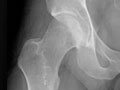

- Radiografías . Se obtienen imágenes de los huesos en una articulación, como la cadera o la rodilla, para determinar si hay daño en el cartílago.

Si tiene las articulaciones sensibles e hinchadas y los músculos débiles, esto también ayudará a que su médico confirme si usted tiene artritis. Usted también podría tener que hacerse radiografías para revisar si tiene daño en las articulaciones. Es posible que su médico desee realizarle análisis de sangre u otras pruebas para determinar si existen otras causas por las que tiene dolor.